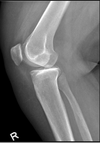

37

what is the most important thing to line up on a lateral knee

articulating surfaces of femoral condyles

38

the medial tibial plateau is __ the lateral tibial plateau is __

medial curved lateral straight

39

correction

more cephalad angle more external rotation

40

more internal lrotation less cephalad angle